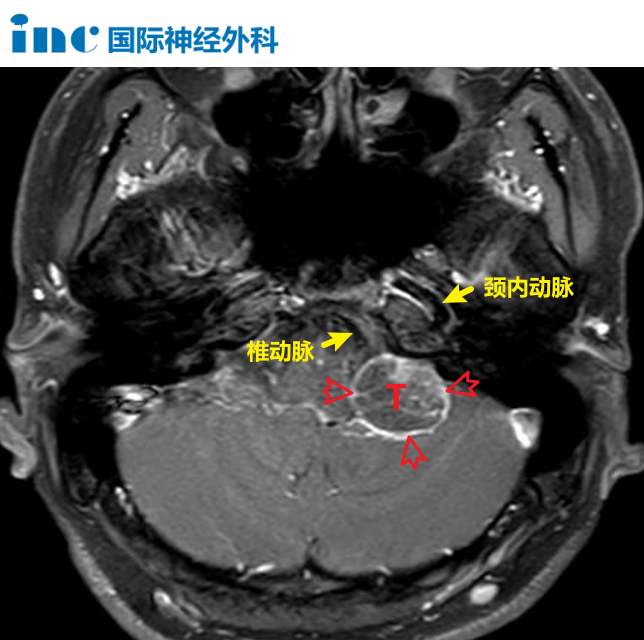

颈静脉孔区位于颅底深处,解剖结构极为繁杂。这里既是后组颅神经、脑干、颈内动静脉汇聚通行的要道,也是公认的手术高风险区域。一旦在手术中造成损伤,轻则出现声音嘶哑、吞咽困难,重则危及患者生命。

2024年6月,巴教授中国行示范手术期间,小凯的手术如约进行。显微镜下,教授如同一位精密的"拆弹专家",在全程保护脑干、后组颅神经及重要血管的前提下,将肿瘤一点点剥离,最终实现全切。

为何这个部位的手术如此之难?颈静脉孔深居颅底,空间极其狭小,内部密集走行着舌咽神经、迷走神经、副神经以及乙状窦、颈内动脉等关键结构。手术要求既做到肿瘤全切,又要保证上述神经血管毫发无损,对术者的显微外科技术、解剖功底和心理素质都是极限层面的考验。